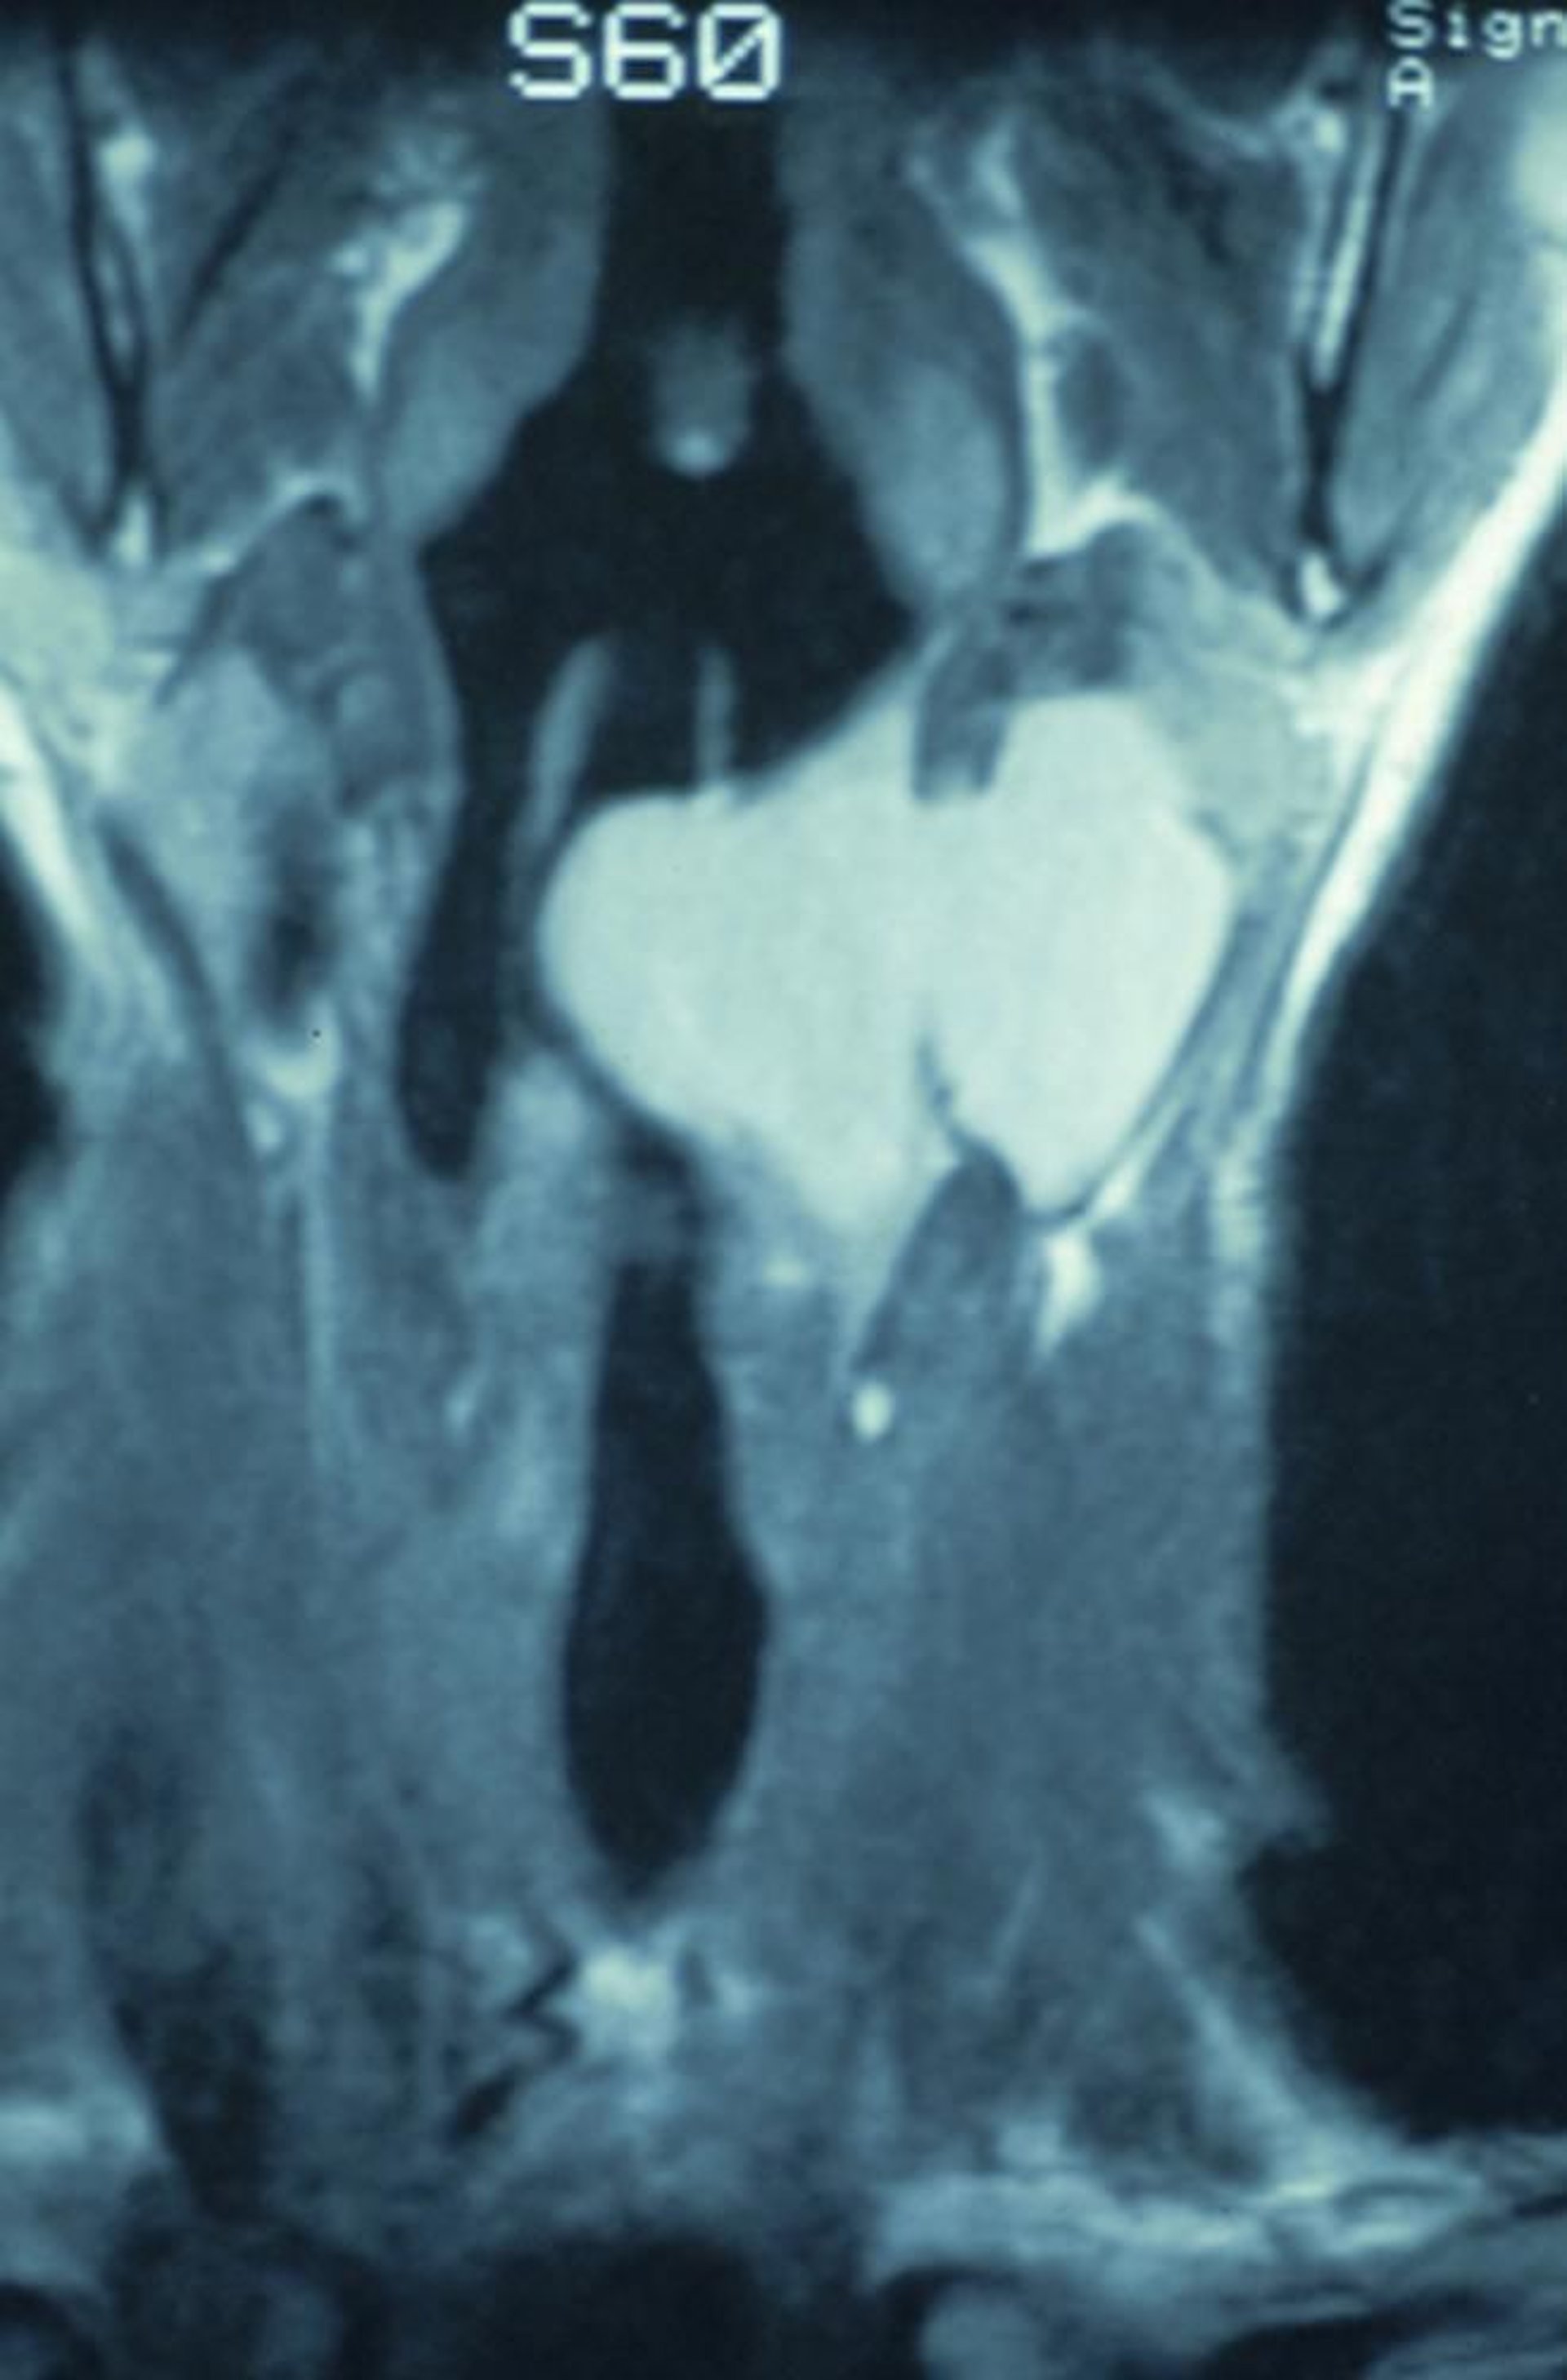

Комбинированное ларингоцеле

Это венечное КТ-сканирование показывает комбинированное ларингоцеле, которое берет начало внутри гортани и распространяется через тиреоидную мембрану, вызывая появление опухоли в шее.

Image provided by Clarence T. Sasaki, MD.